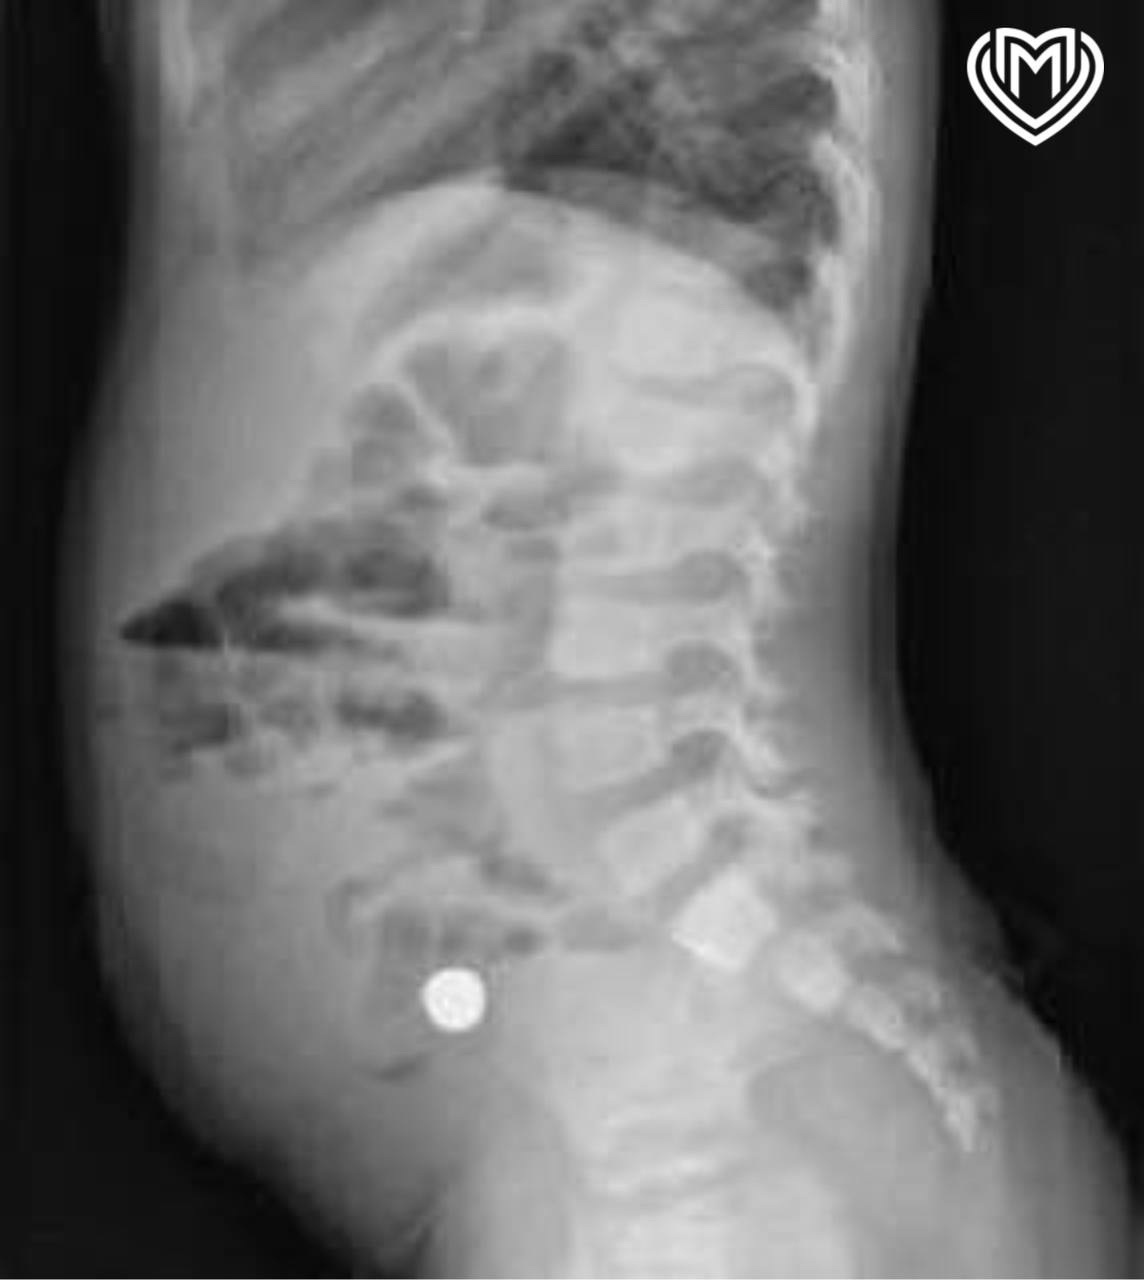

Рентгенография показала, что инородные предметы «стоят» в правой подвздошной области.